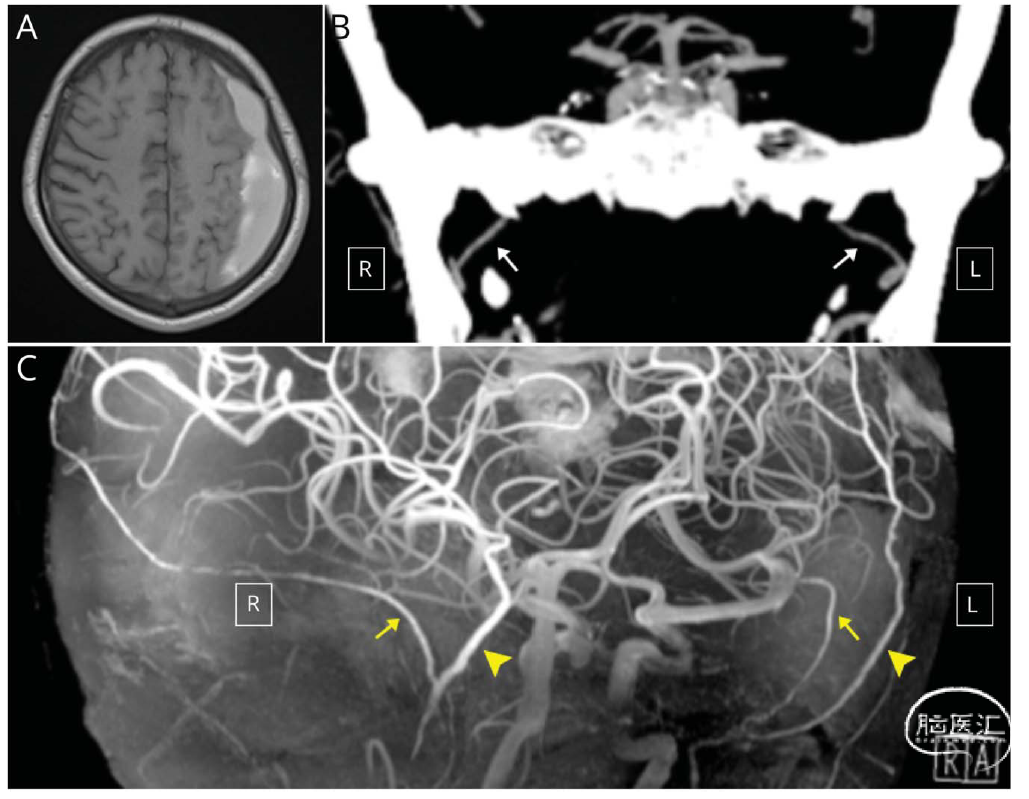

该团队报告了一例65岁左侧CSDH患者的诊疗过程。头颅MRI显示左侧血肿,但CT血管成像和7T高场强磁共振血管成像发现对侧MMA出现“反常增粗征”(图1),提示可能存在异常血供来源。DSA进一步证实,血肿包膜的血供不仅来自同侧MMA,还包括对侧MMA及同侧枕动脉分支(图2A-D)。团队进行了"血肿包膜全供血动脉栓塞",同时栓塞上述所有供血动脉,术后3个月随访显示,血肿完全吸收且未复发(图2E-F)。

图1. 栓塞前影像。(A)7T MRI显示左侧慢性硬膜下血肿(CSDH)。(B)冠状位CT MIP成像显示双侧脑膜中动脉(MMA)(箭头),主干直径分别为1.34mm(左侧)和1.62mm(右侧)。(C)7T MRI TOF成像显示MMA前支(三角箭头)和后支(箭头)。